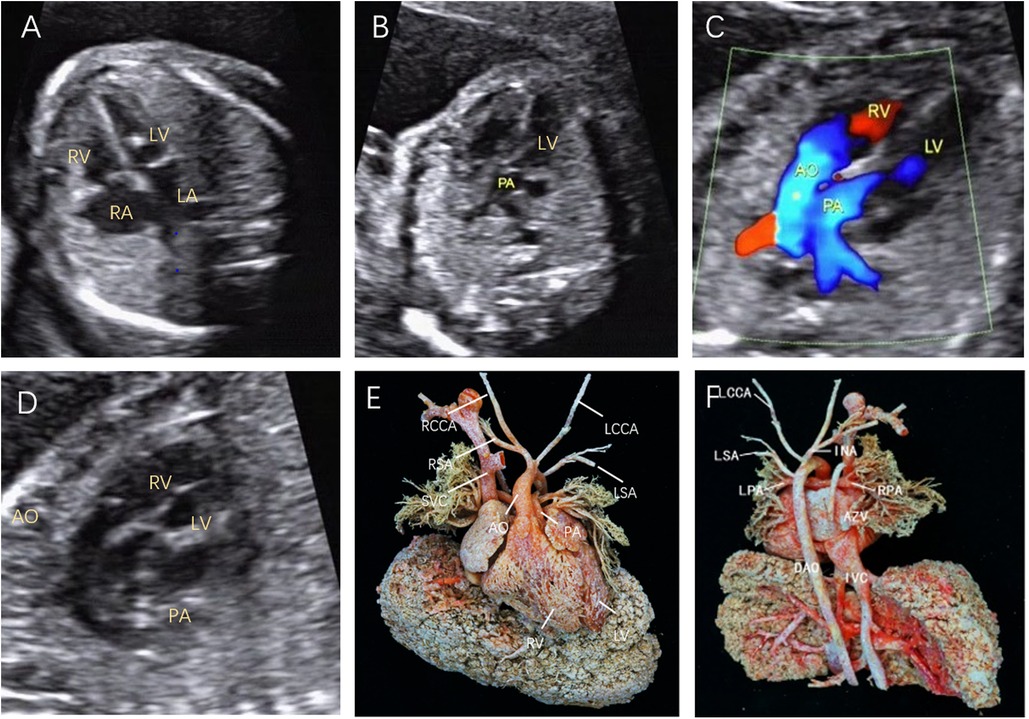

Figure 2. Fetal D-TGA was assessed via echocardiography at 23 weeks and 1 day. (A) Four-chamber view with consistent atrioventricular connections and strong dotted echogenicity of the left ventricle. (B) Five-chamber view showing the pulmonary artery emanating from the left ventricle and bifurcating into the left and right pulmonary arteries a short distance from the beginning of the artery. (C) Two large arteries aligned in parallel, with the aorta emanating from the right ventricle and located anteriorly to the pulmonary artery. (D) Long-axis view of the great vessels: the aortic arch emanates from the anterior right ventricle, followed by the head and neck vessels, which curl backwards in a ‘hockey puck’ shape, and the pulmonary artery follows a ‘crutch’ shape in the long-axis view. (E) Anatomical cast: frontal view. F: anatomical cast: dorsal view.

In this study, we assessed 103 fetuses, initially totalling 121 patients with TGA, with 18 patients lost to follow-up. In early pregnancy, D-TGA exhibited characteristic features, including rightward-bent great vessels in the three-vessel-tracheal view, juxtaposed great vessels in the outflow tract oblique view, and consistent atrioventricular connections in the four-chamber view (Figure 1). In the second trimester, the aorta was connected to the right ventricle, and the pulmonary artery was connected to the left ventricle (Figure 2). In early pregnancy, both arteries ran parallel to the aorta anterior to the pulmonary artery congenitally. CC-TGA patients presented with discordant atrioventricular connections (Figure 3). In the second trimester, there were reversed ventricular positions, parallel outflow tracts, pulmonary arteries from the left ventricle, and the aorta from the right ventricle positioned anterior to the pulmonary arteries (Figure 4). The earliest diagnosis occurred at 12 weeks and 3 days of gestation, and 10 mothers (9.7%) were of advanced maternal age. The TGA distribution included 90 D-TGA patients and 13 CC-TGA patients. Diagnoses were made in the first (8 D-TGA, 2 CC-TGA), second (68 D-TGA, 9 CC-TGA), and third trimesters (14 D-TGA, 2 CC-TGA).